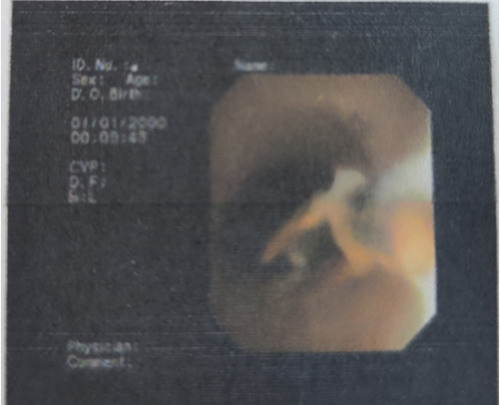

立博体育 全科医学科主任、主任医师肖智权接诊后仔细查看了王瑛的病历资料,完善肺部CT后显示其右下肺大片状阴影,建议该患者做纤维支气管镜检查。检查过程中,发现患者右肺下叶基底支有异物嵌顿,异物周围因滞留时间长已出现肉芽增生及大量脓性分泌物。内镜医师凭借经验和技术,操作纤维支气管镜的活检钳,将嵌顿的异物从患者右肺下叶基底支处完整取出,医生发现取出的异物竟然是一段辣椒尖。